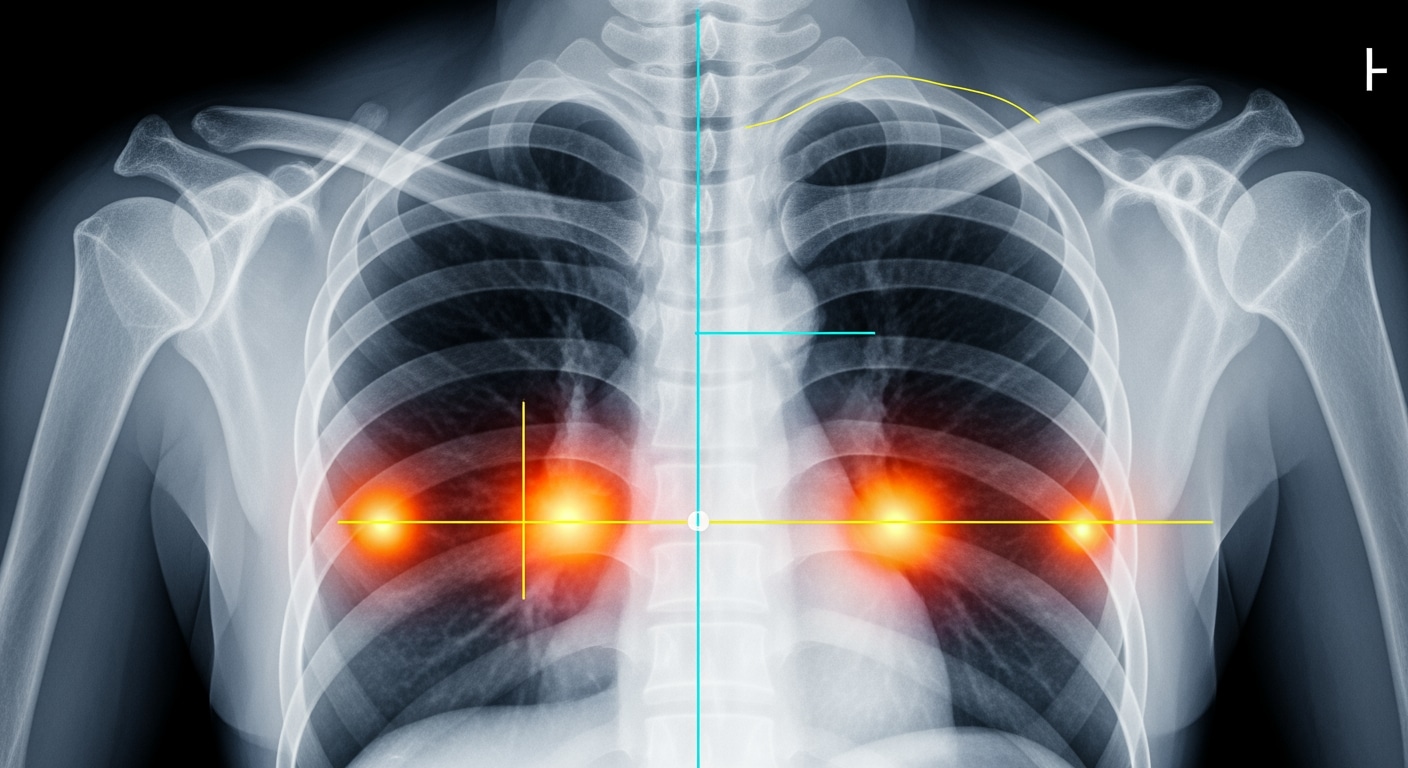

Emergency x-ray services are critical when experiencing severe trauma, suspected fractures, chest pain, difficulty breathing, abdominal injuries, or any condition requiring immediate diagnostic imaging for proper treatment. Priority ER provides 24/7 emergency x-ray imaging with zero wait times, board-certified emergency physicians interpreting results within 10-15 minutes, and advanced digital radiography capabilities. Located at 3800 E 42nd St, Odessa, TX. Call (432) 552-8208 immediately for life-threatening injury symptoms.

The first 30 minutes after severe trauma begins can determine whether a treatable fracture becomes permanent disability or a missed pneumothorax becomes life-threatening respiratory failure[1]. In West Texas, where oil field accidents account for 46% of acute trauma emergencies and motor vehicle collisions increase emergency imaging needs by 192% along Highway 20 and Interstate 20[2], immediate access to emergency x-ray services becomes critical for proper diagnosis and treatment. Priority ER’s board-certified emergency physicians interpret over 5,800 emergency x-rays annually, offering zero wait times and hospital-level radiology diagnostic capabilities that standard clinics and urgent care facilities cannot provide[3].

Unlike traditional urgent care centers that may lack on-site imaging or close at 8 PM, Priority ER operates 24/7 emergency services with immediate access to digital x-ray imaging, advanced radiography diagnostics, and board-certified physician interpretation within 10-15 minutes. Our advanced imaging capabilities[4] ensure diagnostic accuracy while our direct hospital admission capabilities ensure seamless transfer when severe fractures, internal injuries, or chest emergencies require specialized surgical or trauma intervention.

Upon arrival at Priority ER for emergency x-ray services, patients bypass traditional triage delays through our zero-wait protocol. Board-certified emergency physicians trained in trauma medicine begin assessment immediately, utilizing digital radiography systems that produce high-resolution images in seconds rather than minutes[9]. This comprehensive approach identifies life-threatening conditions that general urgent care facilities would miss, such as pneumothorax requiring chest tube, displaced fractures needing immediate reduction, or internal bleeding requiring emergency surgery.

Priority ER's diagnostic capabilities for emergency x-ray services exceed Joint Commission standards for emergency departments[14], featuring digital radiography systems typically found only in major trauma centers. Our x-ray system produces images with 99% diagnostic accuracy compared to conventional film standards, enabling detection of subtle fractures, pneumothorax as small as 5%, and foreign bodies requiring surgical removal[15]. The integration of picture archiving and communication systems (PACS) allows instant image transmission to consulting orthopedic surgeons when complex fractures require specialized surgical planning.

Advanced imaging diagnostics through our comprehensive capabilities include not just standard x-ray views but also CT scanning, ultrasound, and specialized radiographic series for complex trauma evaluation. For patients with multi-system injuries, our imaging department performs trauma series protocols, dedicated spine imaging, and advanced reconstructions automatically, crucial for identifying life-threatening injuries that standard urgent care x-rays cannot fully assess. This technology gap explains why the American College of Emergency Physicians recommends freestanding ERs over urgent care for all significant trauma requiring immediate comprehensive imaging.